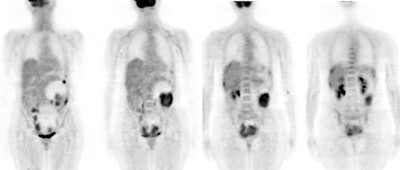

Ovarian cancer: The patient shown below was a 56 year old female who complained of severe abdominal pain. Based upon physical exam ovarian carcinoma was suspected. The patient's CA-125 level was elevated. PET imaging revealed extensive intra-abdominal and pelvic disease including capsular liver metastases. Case courtesy of Northern California PET Imaging Center and CTI. |